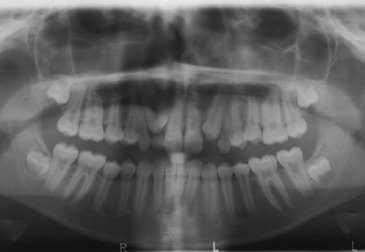

Figure 3 Case 1: Radiological investigation with a panoramic radiograph showing deciduous maxillary canines and right maxillary lateral incisor, as well as mesial eruption of permanent left and right maxillary canines.

An 11-year-old female patient (Figure 1) presented with bilateral MLIA and a 2-mm midline diastema. An intraoral examination revealed healthy dentition and no symptoms or signs of periodontal disease (Figure 2). A panoramic radiograph showed the absence of both maxillary lateral incisors, mesial eruption of the canines, and the presence of deciduous maxillary canines and deciduous right maxillary lateral incisors (Figure 3).